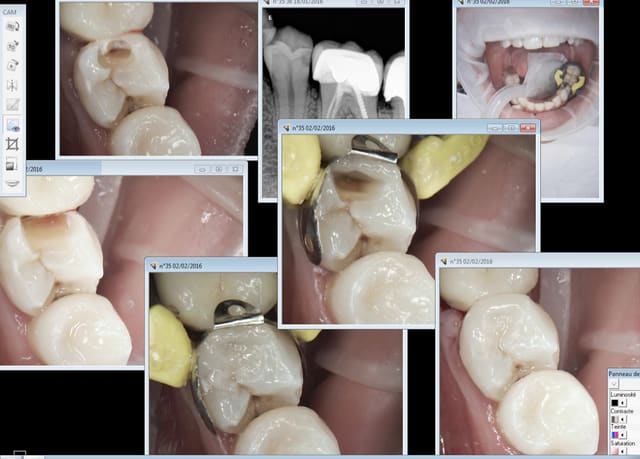

effectivement:l'obturation 3d ne fait pas tout et c'est pour

cela qu'il est préconisé de réaliser l'obturation coronaire le plus vite possible la gutta 3d ne fait pas tout;bon je vois mes résultats sur 33 ans d'exercice libéral j'ai posté qq. bio et RTE ;la reproductibilité des mes endo. date de l'époque oû j'ai compris que la digue était indispensable;une

désinfection à l'hypo.est indispensable quelque soit la méthode d'alésage ;l'obturation 3d fortement conseillée

autrement la meilleure endo est de garder la dent vivante!!!

d’où onlay emax etc...